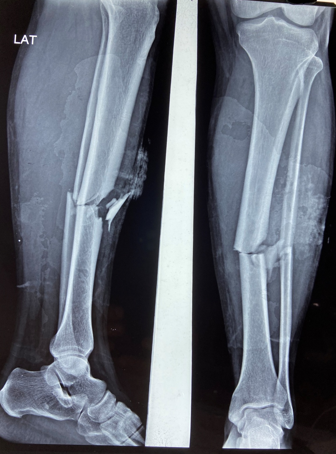

In a series of delayed union with internal fixation over 47 patients regardless of the fracture sites communition or inadequate fixation, had union in all patients including a case of infected nailing of femur. These patients had reported to Dr. S S Jha three to seven months after internal fixation at other centers. None of these patients were willing to submit themselves for further surgical intervention. Teriparatide 20mcg daily through subcutaneous route was started in all patients with adequate supplementation of vitamin D and calcium. Evident radiological bony union was perceptible after three months with clinical improvement in the initial presenting symptoms of the patients and the osseous consolidation was invariably observed radiologically within four to six months. It was only in six patients that Teriparatide was continuously used for one and half years for reasons of general debility, elderly age and osteoporosis. Radiographs of three difficult cases are being displayed from the series.

Case 1([Figure 1], [Figure 2], [Figure 3], [Figure 4], [Figure 5], [Figure 6], [Figure 7], [Figure 8], [Figure 9])

- Case 1([Figure 1], [Figure 2], [Figure 3], [Figure 4], [Figure 5], [Figure 6], [Figure 7], [Figure 8], [Figure 9])